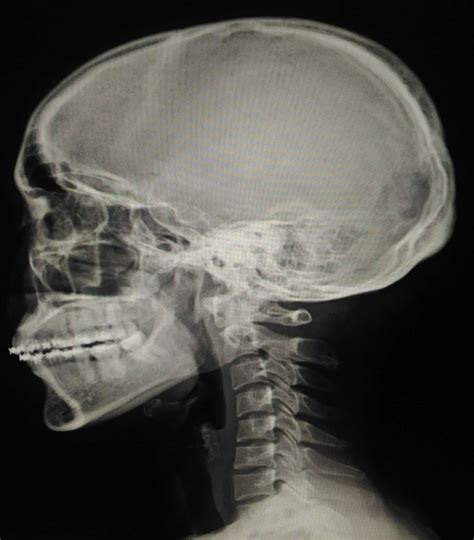

• Medical Imaging Techniques: The program covers various imaging modalities, including X-rays, computed tomography (CT), magnetic resonance imaging (MRI), and ultrasound. Students gain hands-on experience operating these machines and interpreting the resulting images.